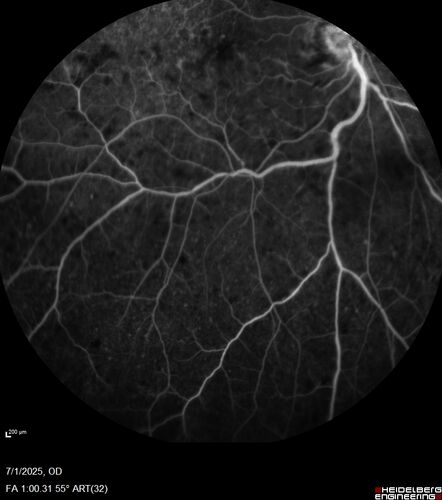

Hemi-CRVO - dual trunk vein

81 year old female mild vision loss - Anatomy shows dual trunk vein with one blocked. About 20 percent of people have this anatomy